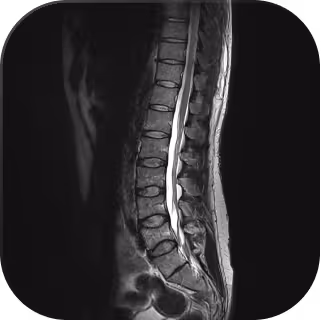

The MRI machine we use will depend on the facility you're booked into, but all of them are 1.5 Tesla (1.5T) MRI machines, which are widely used in clinical settings for high-quality imaging.

A quick scan that takes 5–10 minutes, with a short breath-hold. There are no needles or contrast dyes, and it's over quite fast. - Whole-Body MRI (no contrast)

This part takes around 40–50 minutes. It’s non-invasive and open at both ends, but you’ll hear loud knocking sounds during the scan. It’s important to stay still so the images come out clearly.

A targeted MRI may offer finer detail on a specific body part, but it only looks where you already know to look, meaning it relies on something already being wrong. A full-body MRI flips that approach, scanning 100+ anatomical regions in one session to catch serious conditions like early-stage cancers and aneurysms before symptoms ever appear.

The resolution is more than sufficient to detect clinically meaningful findings, and if anything is flagged, our radiologists and specialty GPs at Everlab will guide you on next steps, including targeted follow-up imaging if a closer look is needed. Think of it as the wide-angle lens that ensures nothing is missed, with the ability to zoom in whenever necessary.